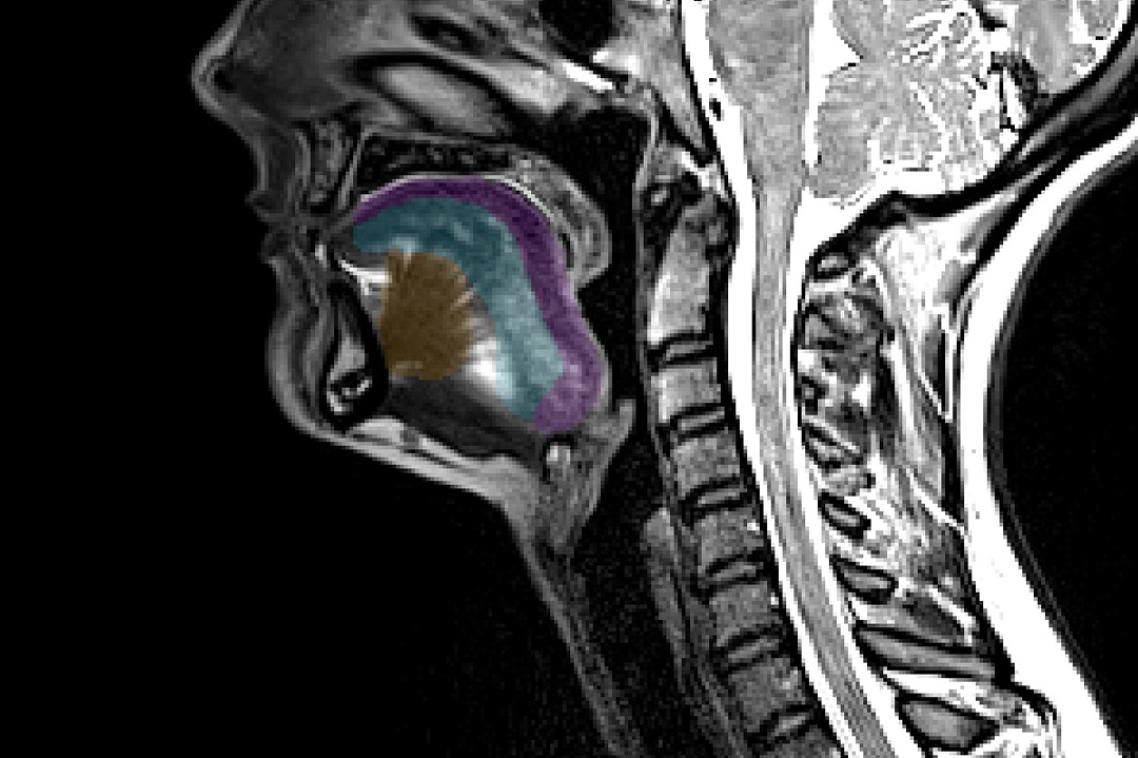

Researchers at The University of Queensland have shown how Botox – also known as Botulinum neurotoxin serotype A – is transported via our nerves back to the central nervous system.

“For the first time, we’ve been able to visualise single molecules of Botulinum toxin travelling at high speed through our nerves,” Dr Wang said.